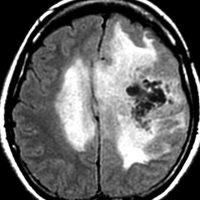

80代の女性に偶然見つかったものです。右の島のグリオーマ insular gliomaで,ガドリニウム増強されないびまん性グリオーマです。右側は2ヶ月半後のMRIで,とても早く広がっていますので,生検術をしました。組織診断は,壊死や微小血管増生はなく,びまん性星細胞腫グレード2でした。TERT promotor mutant, IDH1 WT, IDH2 WT, H3F3A-K27 WT, H3F3A-G34 WT, m HIST1H3B WT, 1p/19q intact, CDKN2A/2B negativeです。

この例は,molecular GBMつまり,glioblastoma IDH-WT WHO grade 4と診断されます。